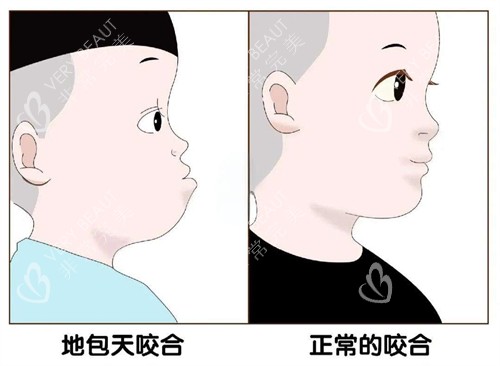

一、“地包天”二十年,我到底在怕什么?

“你这下巴,再长点能当铲子了。”小学同桌这句话,我记了十年。从小到大,“地包天”三个字像根刺,扎得我抬不起头:拍照永远抿嘴笑,吃饭不敢张大嘴,连笑都不敢露齿——怕别人盯着我的下巴看。

“地包天”真的只是“丑”吗?

——不,是每次拍照都要找角度的疲惫,是别人盯着你下巴看时的尴尬,是连笑都要先想“会不会太奇怪”的纠结。

后来才知道,正颌手术分两种:一种是单纯牙性“地包天”,戴牙套就能矫正;另一种是骨性“地包天”,下巴骨头比上颌突出,必须动骨头。而我,属于后者。